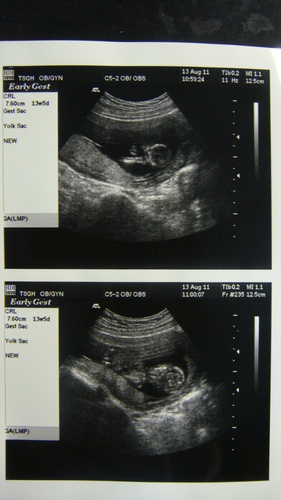

今天忘了帶相機去錄影~不過有拿到超音波照片

北鼻又大了點(真是一暝大一寸) 不過進度依舊超前一些些~7.6 cm(是13W5D的大小...明明是13W)

預產期又不一樣了~三總給我的預產期是2/21(之前謝醫師是給2/19)

沒有拍全身(可能是因為這次要照頸部透明帶的關係)

不過紙質比較好~是亮面的~跟婦產科給的霧霧的質感不一樣